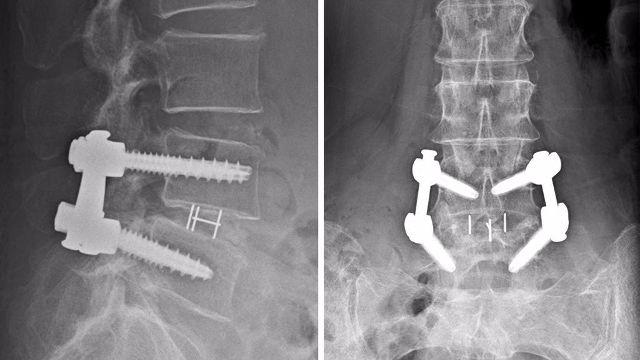

去年,她在陈笃生医院接受微创脊椎外科手术,手术过程中,外科医生在她下背部开了个不到3公分的切口。手术完成两天后,她就能在别人协助下走动,不再受疼痛的折磨。

新加坡国立脑神经医学院神经外科顾问医生Colum Nolan说, “在以前的传统手术中,外科医生会开个大约10到20公分的切口,不过有了先进技术,可以更局部化,更精准地治疗神经压迫疾病。外科医生能通过小切口进行手术,限制背部肌肉附带损伤的范围。研究显示,这种方式会减少流血、伤口感染的风险,也能更快康复。”

Jacob Oh 兼职助理教授说,较新的科技包括电脑导航系统,外科医生在进行手术时可以通过CT扫描装置,来引导放置螺丝的位置,准确度到97%。

脊椎手术也采用内窥镜“相机”系统,外科医生能瞄准到脊椎细微部位,只需通过皮肤的小切口就能进行手术。